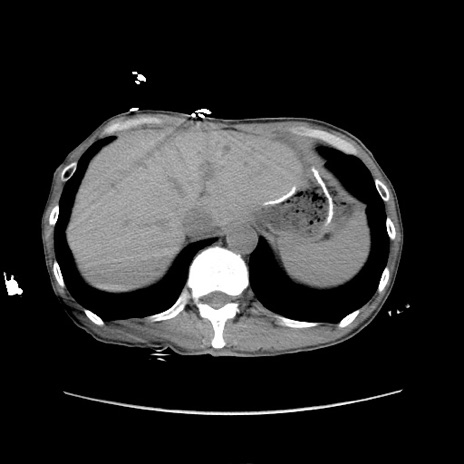

症例11(横断像)

【症例】 60歳代男性

【主訴】 下腹部痛

【現病歴】 本日夜中より下腹部痛の症状認め、受診。

【既往歴】 膀胱癌(膀胱全摘+尿管皮膚瘻術) 、胃癌術後

【身体所見】 BT 35.3℃、PR 58/min、BP 136/98mHg、腹部平坦、軟、腸蠕動音±、ストマ留置あり、左上腹部~正中部に圧痛あり、反跳痛なし。

【データ】WBC 5100、CRP0.01